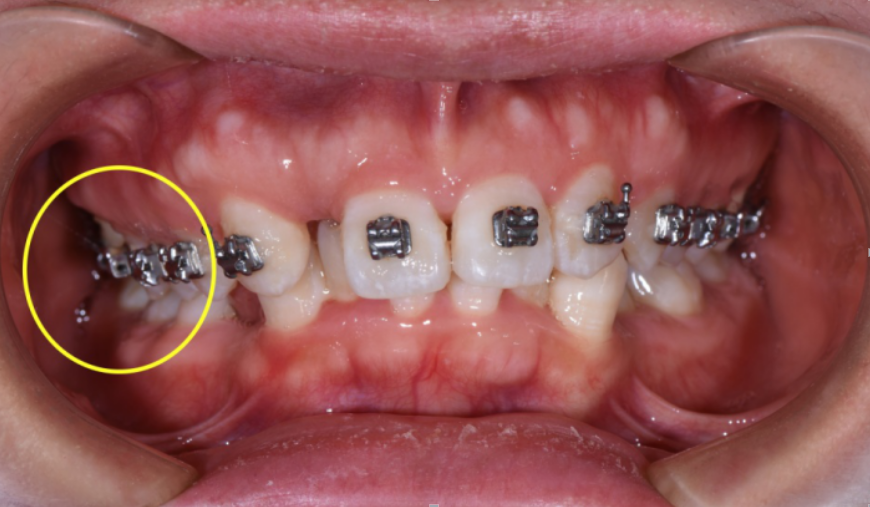

矫正中解决锁合

矫正中解决锁合

矫正中解决锁合